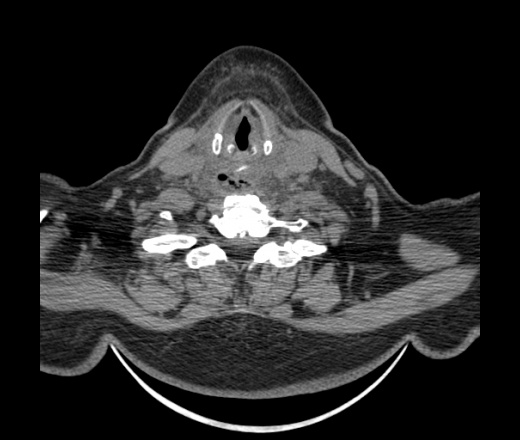

Женщина поступила в х/о спустя 4 дня после того как при употреблении карася подавилась костью.

Наличие газа в средостении на протяжении тел С2-С6 (медиастинальна эмфизема); рыбная кость на уровне тела С6.

При всем уважении, но говорить о медиастинальной эмфиземе, оценивая мягкие ткани шеи, как-то слишком резко. На мой взгляд, это ретрофарингеальное пространство.

Эвакуировали почти 100мл гноя. Но кость не смогли найти. Думаю что она даст дальнейшее ослоднение. Эндоскопически за черпалонадгортаной звязкой не смогли зайти в пищевод, все мягкие ткани отечные, просвет пищевода сдавлен. По всей видимости параэзофагеальная клетчака тоже задействована. Эмпиема, если ее можно так назвать, незнаю как правильно дошла до уровня яремной вырезки. Чем закончиться напишу. Ждем медиастинита.

Согласен с Вами; конечно, наличие газа в клетчатке ретрофарингеального пространства (затмение с опечаткой..). К сожалению, процесс "продвигается" к медиастиниту. Но почему никто, не отмечает наличие рыб. кости; или это для Всех очевидно?

Кость то мы сразу выявили, размеры где то 17*2мм, но ее так и не получается найти в этой каше